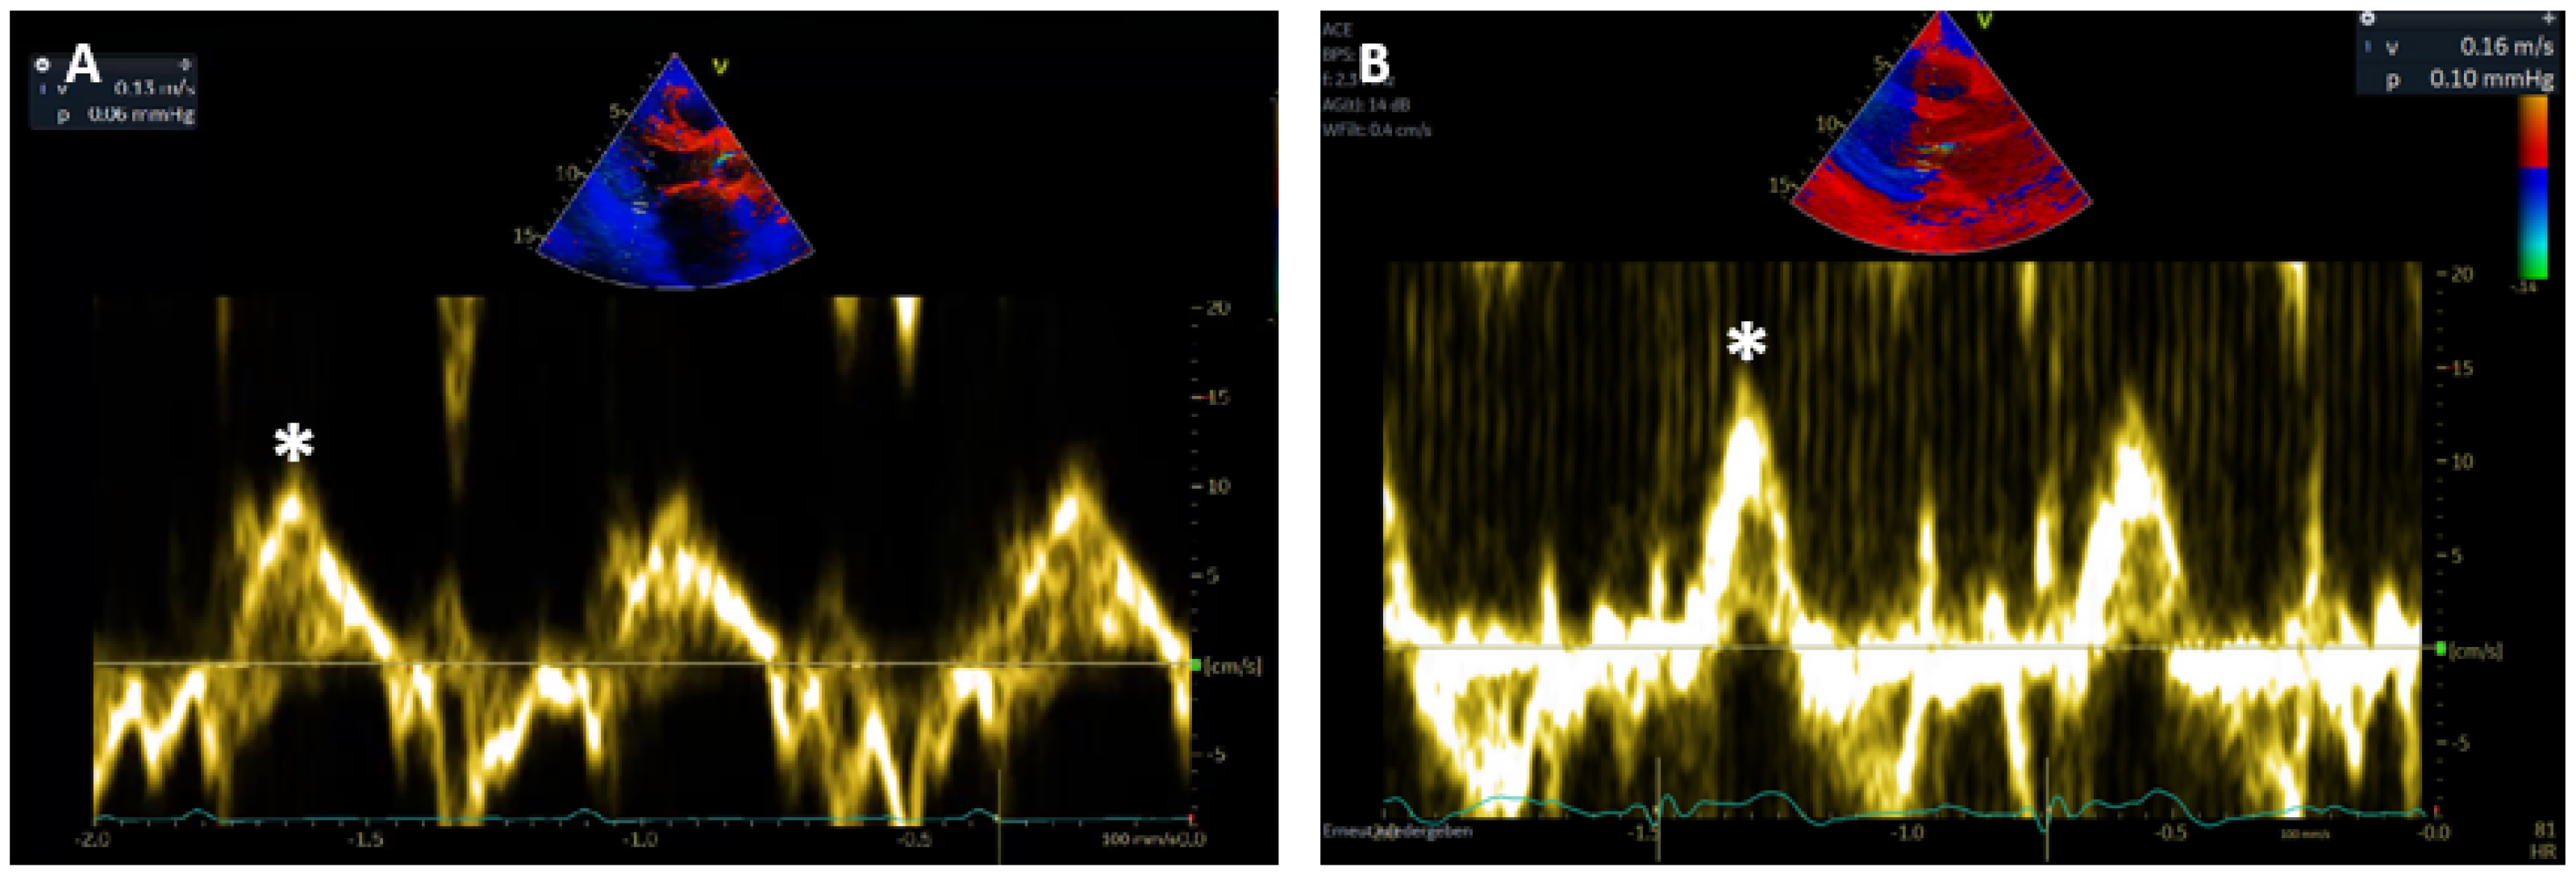

3.4. Sm Course after OHT